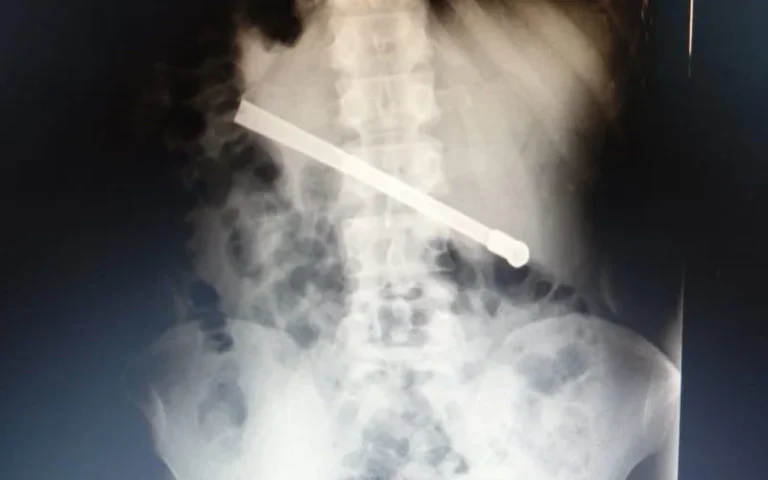

Rosario: Un preso se tragó una bombilla y tuvieron que operarlo para sacársela

Un interno que se encuentra detenido en el Complejo Penitenciario Rosario debió ser derivado al hospital Eva Perón, ya que … Sigue leyendo Rosario: Un preso se tragó una bombilla y tuvieron que operarlo para sacársela